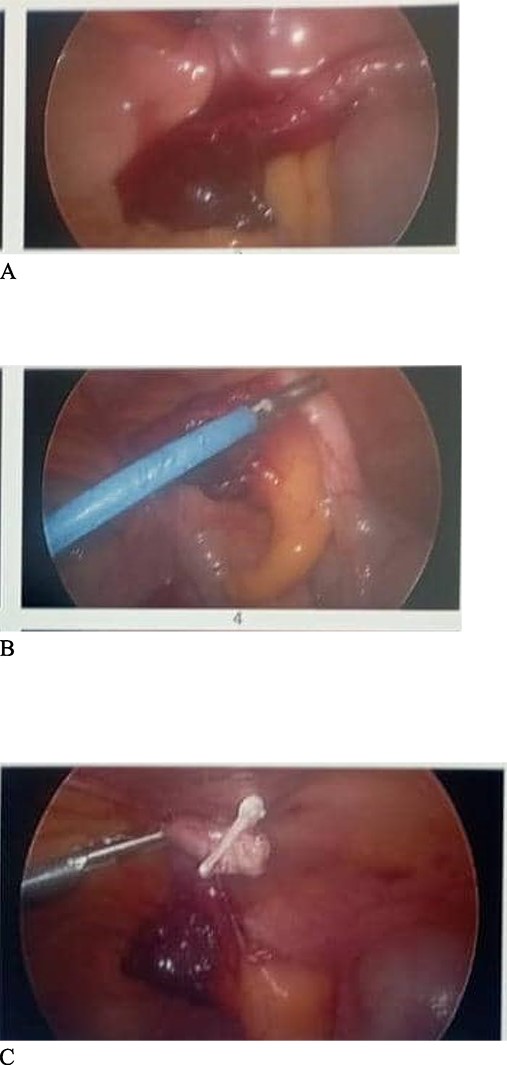

Due to the pre-operative CT scan findings of a sac containing appendix, we decided to perform a laparoscopy. At laparoscopy, a gangrenous distal half of the appendix and mesoappendix was encountered (Fig. 2). Appendicectomy was done laparoscopically and the abdominal cavity lavaged with saline. Postoperatively, she was started on soft diet. She recovered well and was discharged after 24 hours of postoperative monitoring. Histology showed a fibrotic appendix.

Findings at laparoscopy. (A) Distal end of the appendix herniating through the abdominal wall into the canal. (B) Appendix being pulled out of the abdominal wall defect. (C) Appendicectomy done after dissecting the mesoappendix and clipping the base of appendix with haemolock clips.

De Garengeot hernia presents as a lump in the groin. The risk of incarceration is high due to the narrow femoral defect which can result in extraluminal compression of the appendix causing acute appendicitis. This possibly explains the presentation and the intra-operative findings in our index case (Fig. 2). One meta-analysis involving 90 cases reported the incidence of appendicitis in the sac to be 84% [5]. While patients may present with localized abscess and toxicity, generalized peritonitis is however rare presumably due to the narrow neck limiting the inflammatory process to the femoral canal [6].

Open femoral hernia repair with open appendicectomy has been reported to be the commonest approach as documented in two systematic reviews [2, 5]. However, in our case, only an empty sac was encountered during the dissection, the appendix had reduced spontaneously. With a high index of suspicion, we decided to perform a diagnostic laparoscopy which then revealed a gangrenous appendix (Fig. 2).